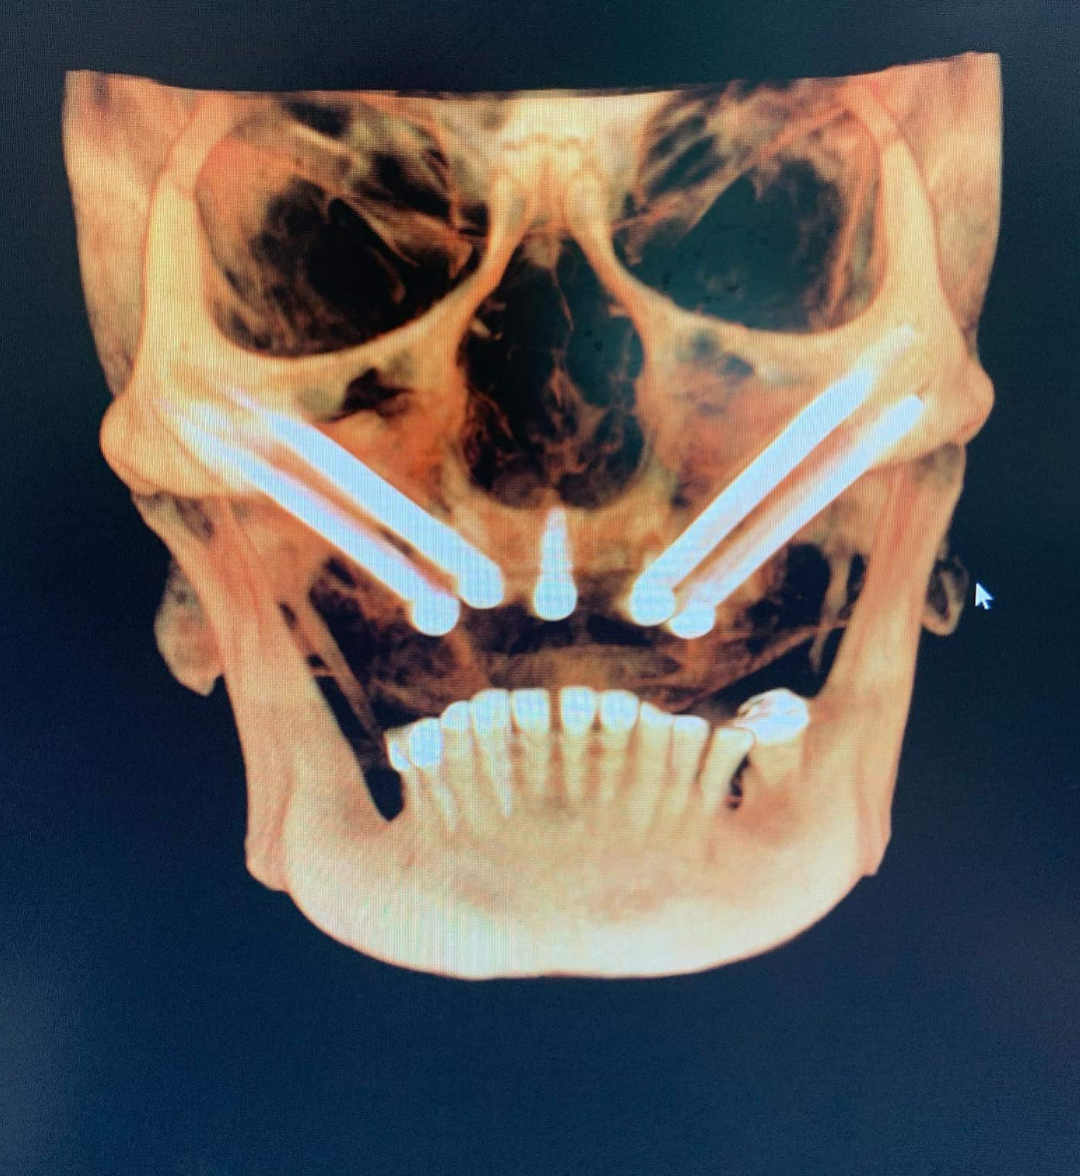

此类种植体用于上颌骨量不足患者的无牙颌修复,可作为All-on-4/X全牙弓修复方案的锚定基台。最终修复体通常采用氧化锆材质制作。

经鼻种植体主要用于替代上颌四颗颧骨种植体(quad zygoma)的植入方案。四联颧骨种植仅适用于鼻下骨量极度匮乏的极端病例。该技术的核心目标是通过在前牙区植入1-2颗经鼻种植体,避免使用4颗颧骨种植体。

尽管经口入路植入鼻骨的方式看似非常规,但其优势显著:相较于四联颧骨种植,该技术不仅能提供更强的骨结合强度,还具有更低的手术风险。由于四颗颧骨种植体常面临空间不足的难题,此时经鼻种植体便展现出独特的临床价值。